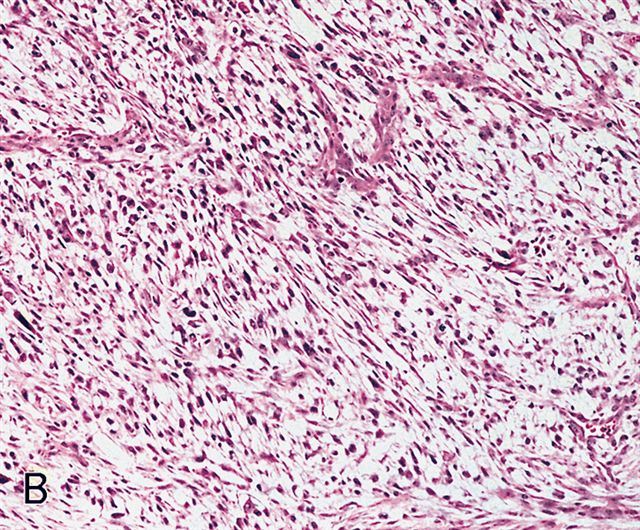

Microscopic (histologic) description

- Sheets of large, atypical and frequently multinucleated polygonal, spindled or rhabdoid eosinophilic cells (Am J Surg Pathol 2009;33:1850)

- Cross striations are seldom detected

Microscopic (histologic) images

Differential diagnosis

- Undifferentiated pleomorphic sarcoma: